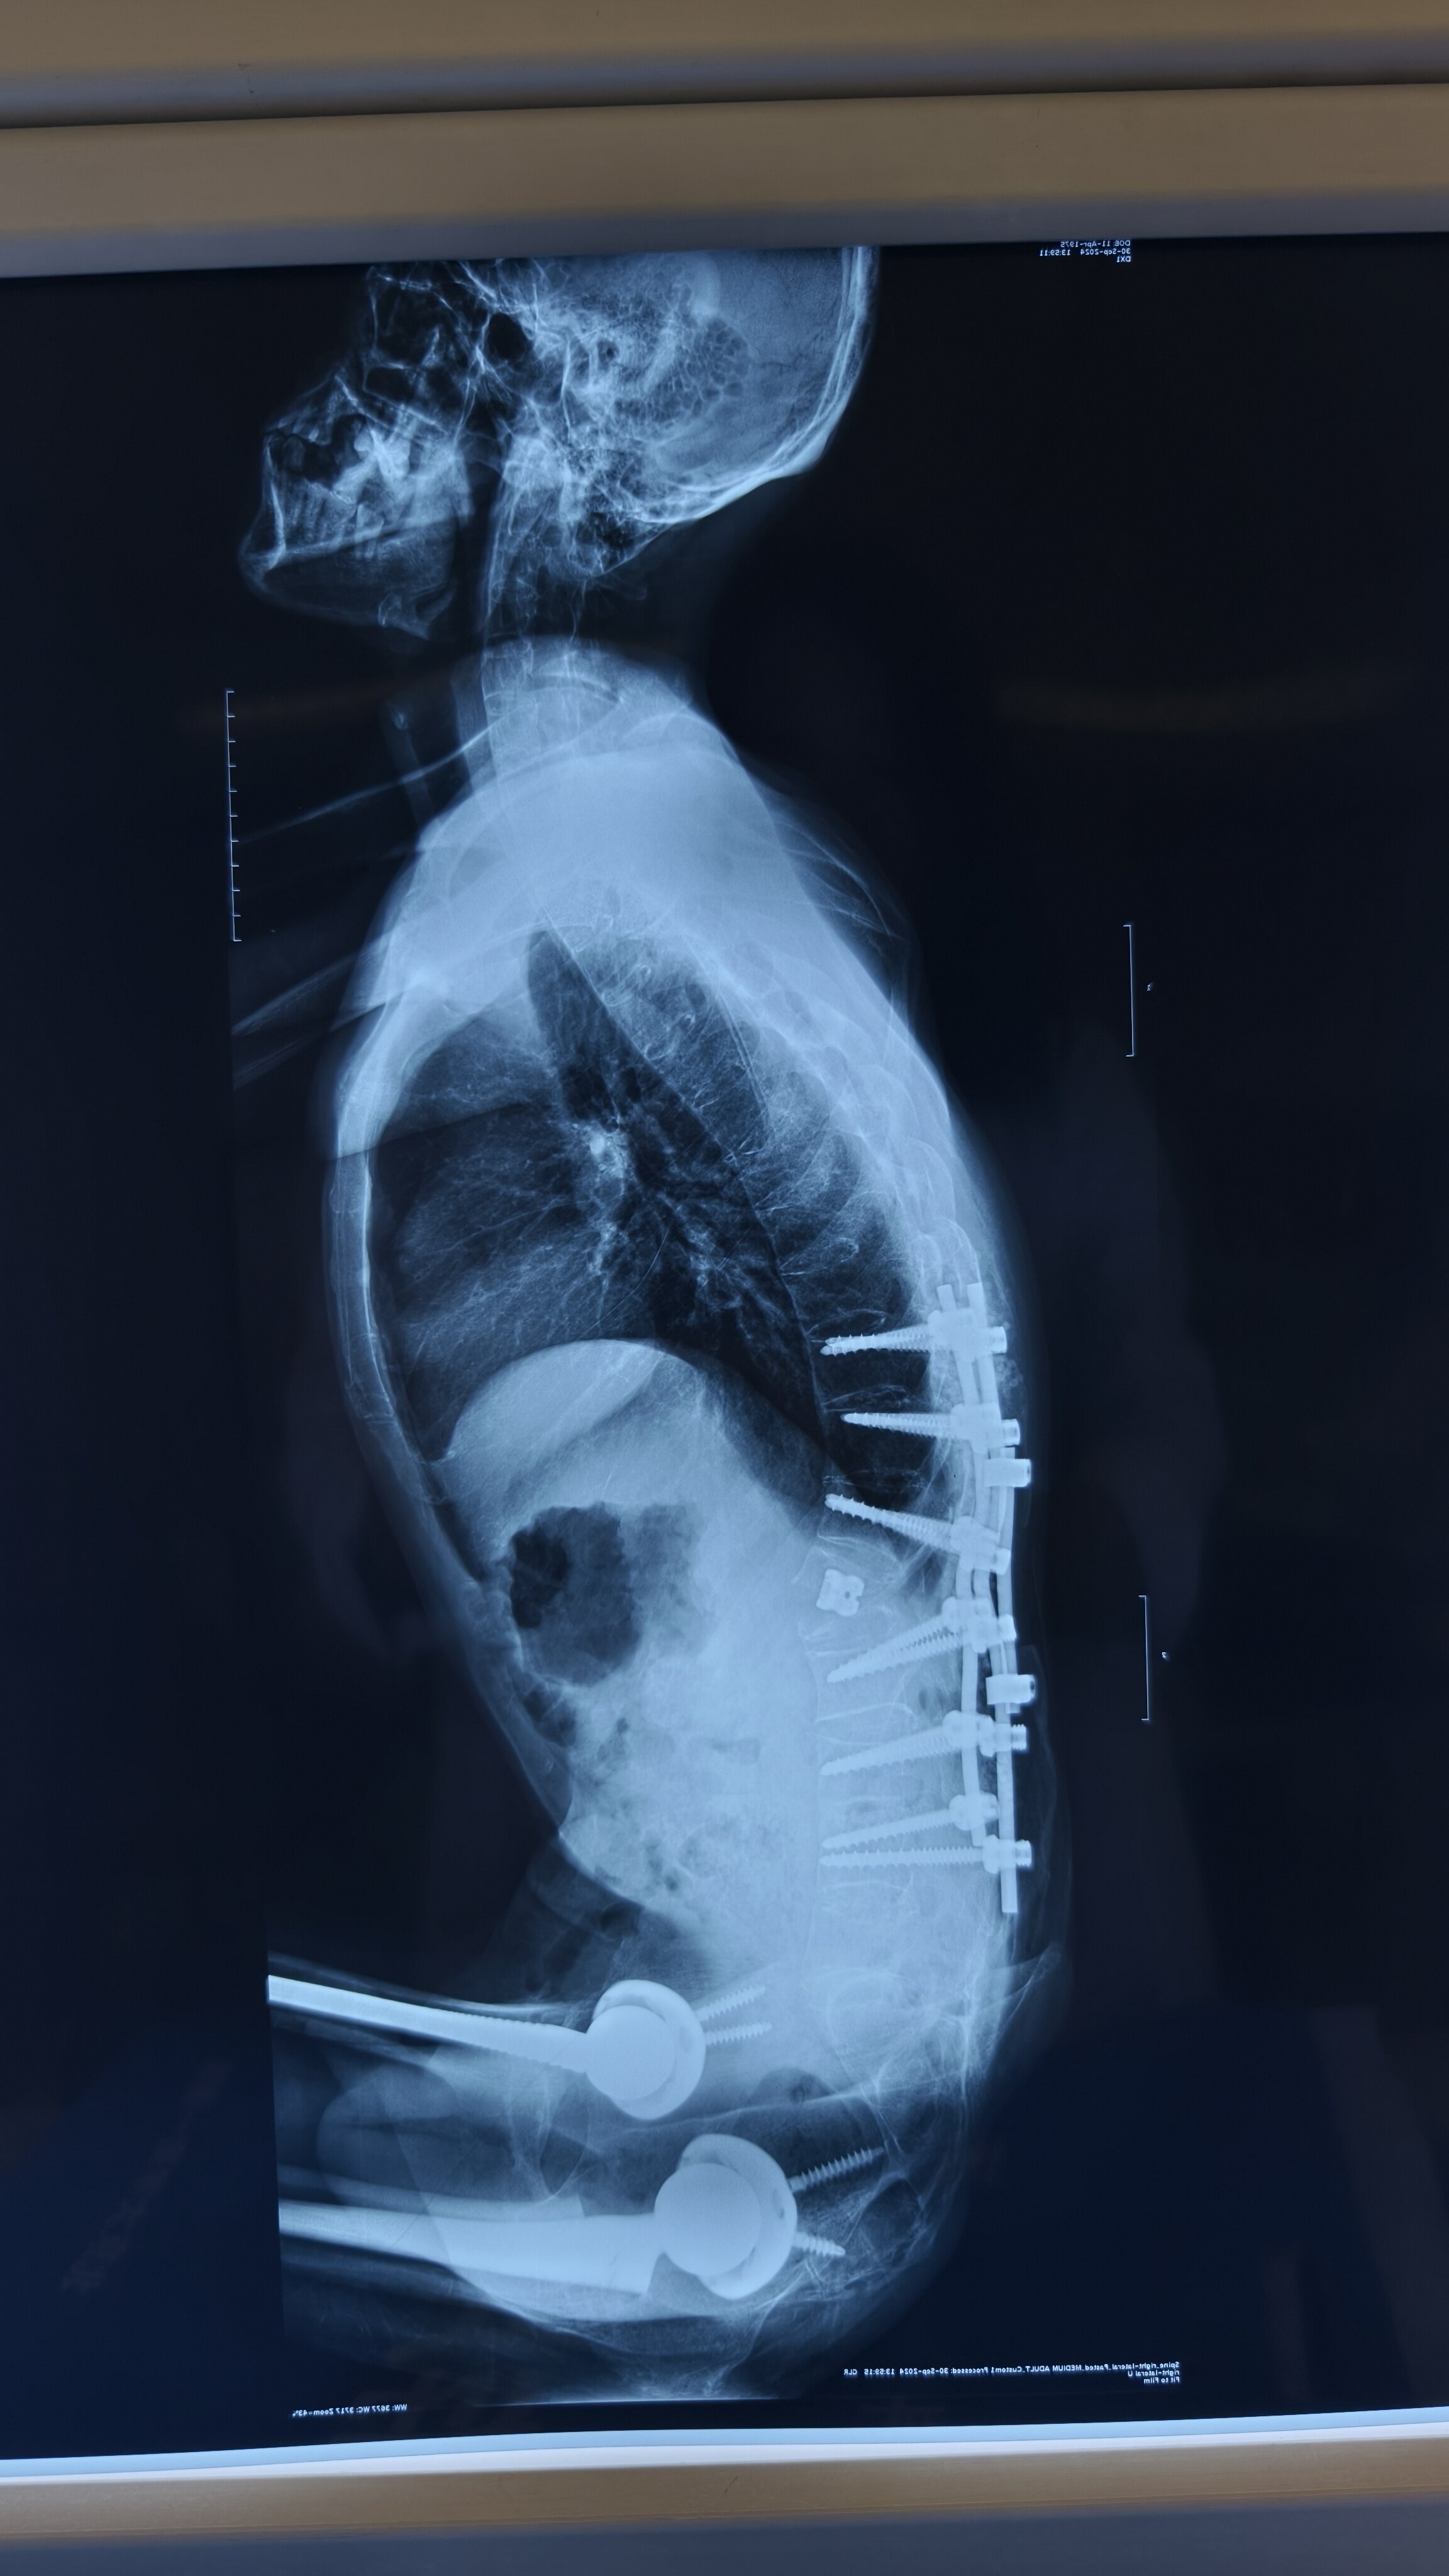

重度强直性脊柱炎治疗案例

图片尺寸2304x4096